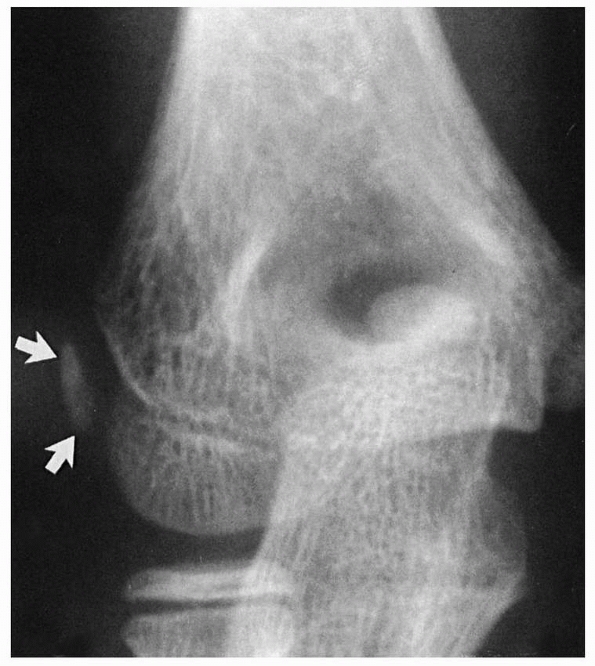

lateral epicondyle, and trochlea fuse to form one epiphyseal center.

Metaphyseal

bone separates the extra-articular medial epicondyle from this common humeral epiphyseal center (Fig. 13-7).

FIGURE 13-7

The secondary ossification centers of the lateral condyle, trochlea, and lateral epicondylar apophysis fuse to form one center (white arrows). This common center is separated from the medial epicondylar apophysis by advancing metaphyseal bone (black arrows). |